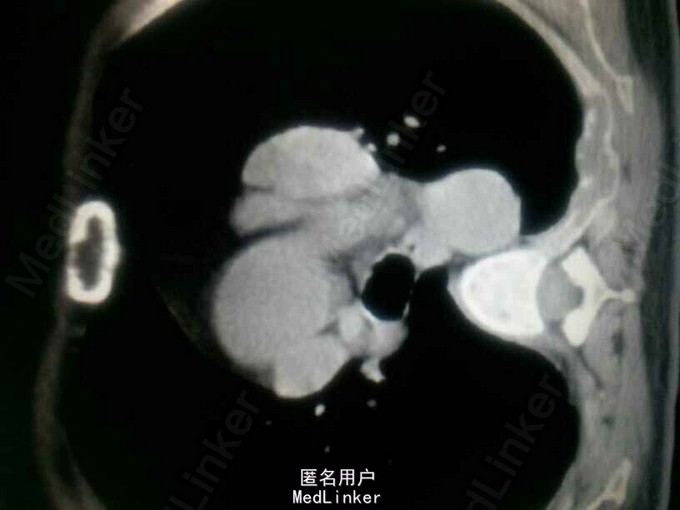

入院后查钾:2.63,钙:3.72,同时尿素氮14.23,肌酐140,碱性磷酸酶672。同时B超提示双肾多发结石。即考虑甲旁亢可能。行PTH:2143。基本明确确诊甲旁亢。但查双侧甲状旁腺B超正常。胸部增强CT提示主动脉弓旁软组织肿块影,双侧多发肋骨骨质破坏。甲状旁腺显像:左胸局部放射性异常摄取。 诊断:异位甲状旁腺肿瘤,甲旁亢,高钙血症,肾结石,病理性骨折。 予降钙等治疗后行剖胸纵膈肿瘤切除术